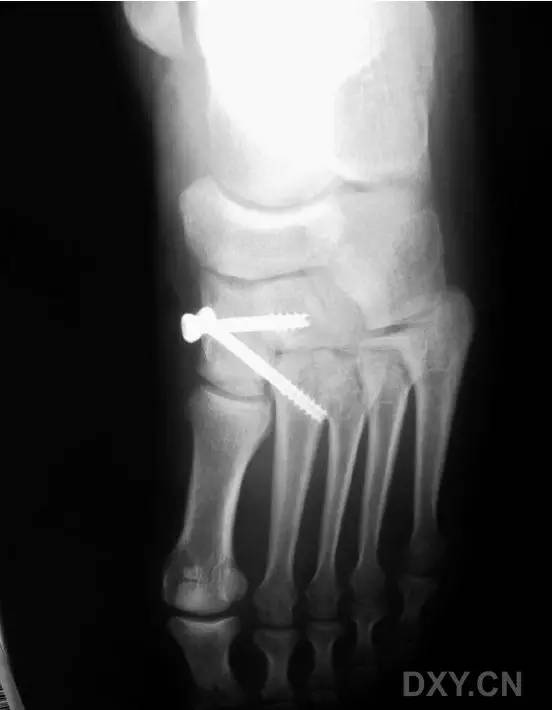

这一损伤的传统固定方式是将 1 枚螺钉(以下简称为 Lisfranc 螺钉)经内侧楔骨向第 2 跖骨基底置入(图 1)。

图 1. 传统的 Lisfranc 螺钉置入方法

然而这种固定方式存在一大缺陷,那就是,一旦出现螺钉的断裂,将导致螺钉头端取出困难(图 2)。

图 2. 传统 Lisfranc 螺钉置入后,螺钉断裂,位于第 2 跖骨基底的螺钉尖端难以取出